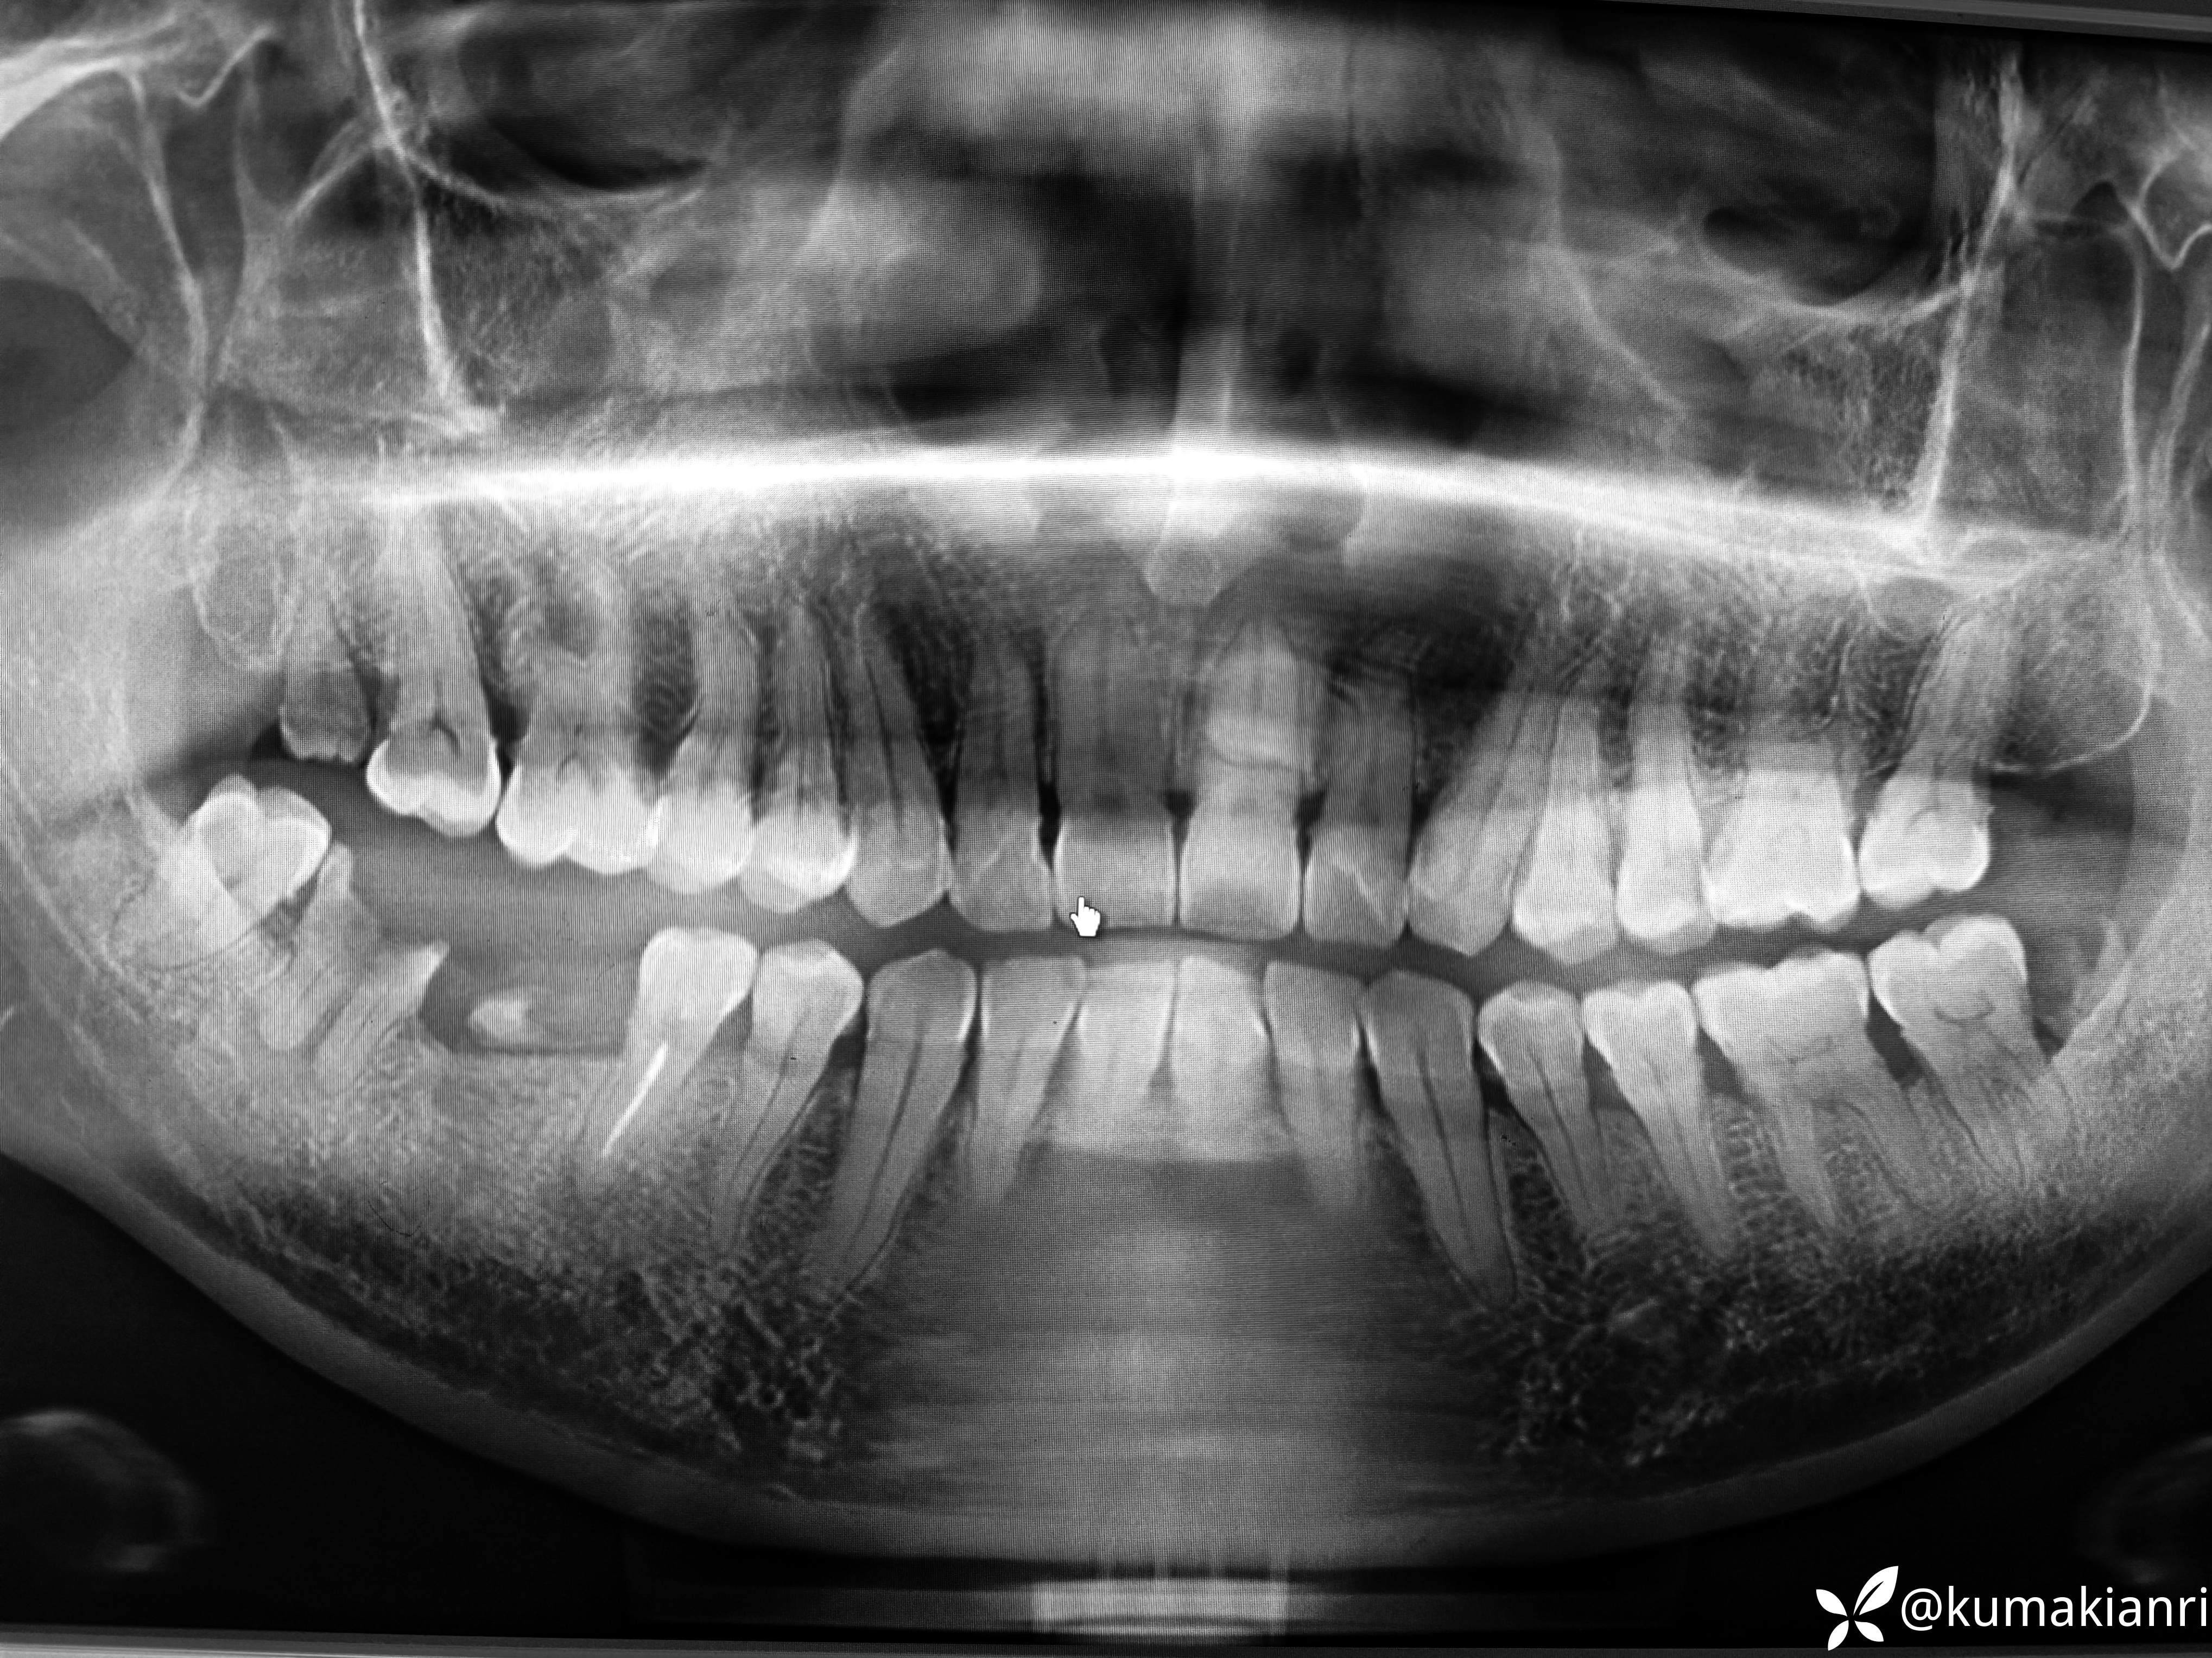

检查:37叩诊+,冷+,牙龈萎缩3-4mm,根颈1/3暴露,远中邻面龋坏;38牙冠大面积龋坏